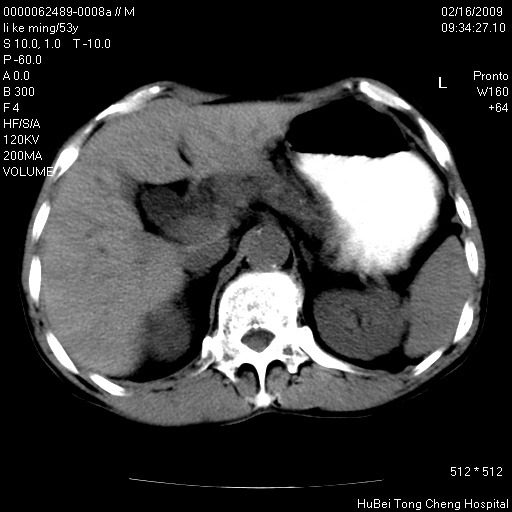

以下是引用卜一在2009-2-16 16:13:00的发言:[br]胰胆管扩张,末端明显狭窄 梗阻,胰头及十二指降段壶腹部结构紊乱。多考虑:十二指降段壶腹部癌!

以下是引用dyqct在2009-2-16 16:58:00的发言:[br]胰头内斑点状及结节状高密度影是钙化灶还是其它?以往做过什么治疗?

以下是引用zsl6918在2009-2-17 8:48:00的发言:[br]符合胰头癌侵犯十二指肠。